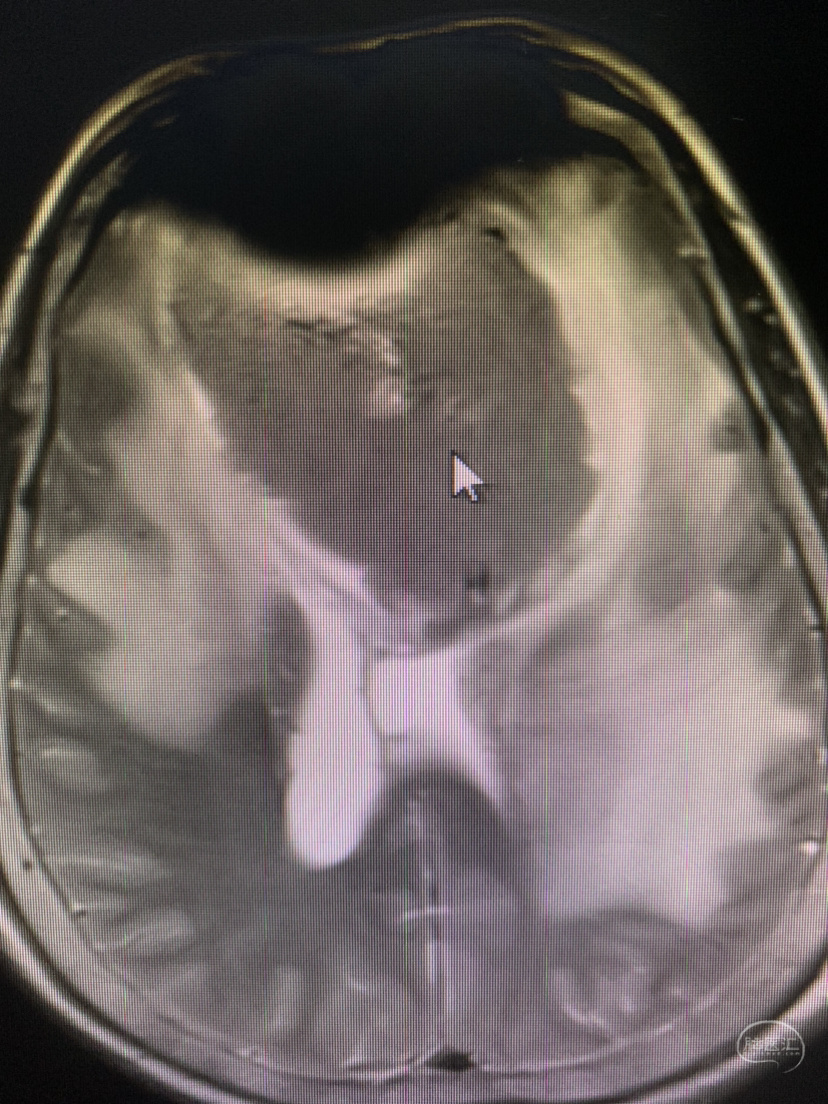

术前术后对比